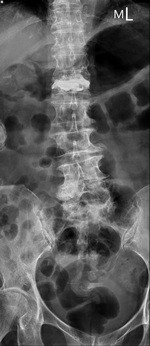

右圖:陳阿嬤脊椎灌骨水泥術後X ray。